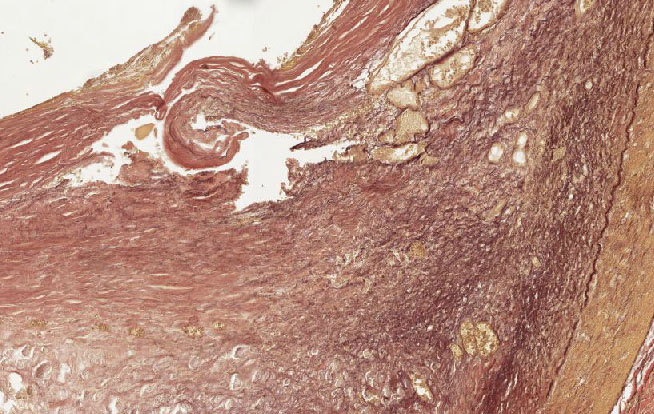

• Organdiagnose: Koronararterie

• Querschnitt einer Koronararterie mit arteriosklerotischer Plaque

• subtotale Stenose durch inkompletten thrombotischen Verschluss

• Thrombus: schon teilweise organisiert

• Lamina elastica interna und Media intakt, bei dem Plaque handelt es sich um eine subendotheliale Läsion

Abb. 426: Subintimaler Plaque und zentrale Thrombose (rechts). Die Media ist intakt.